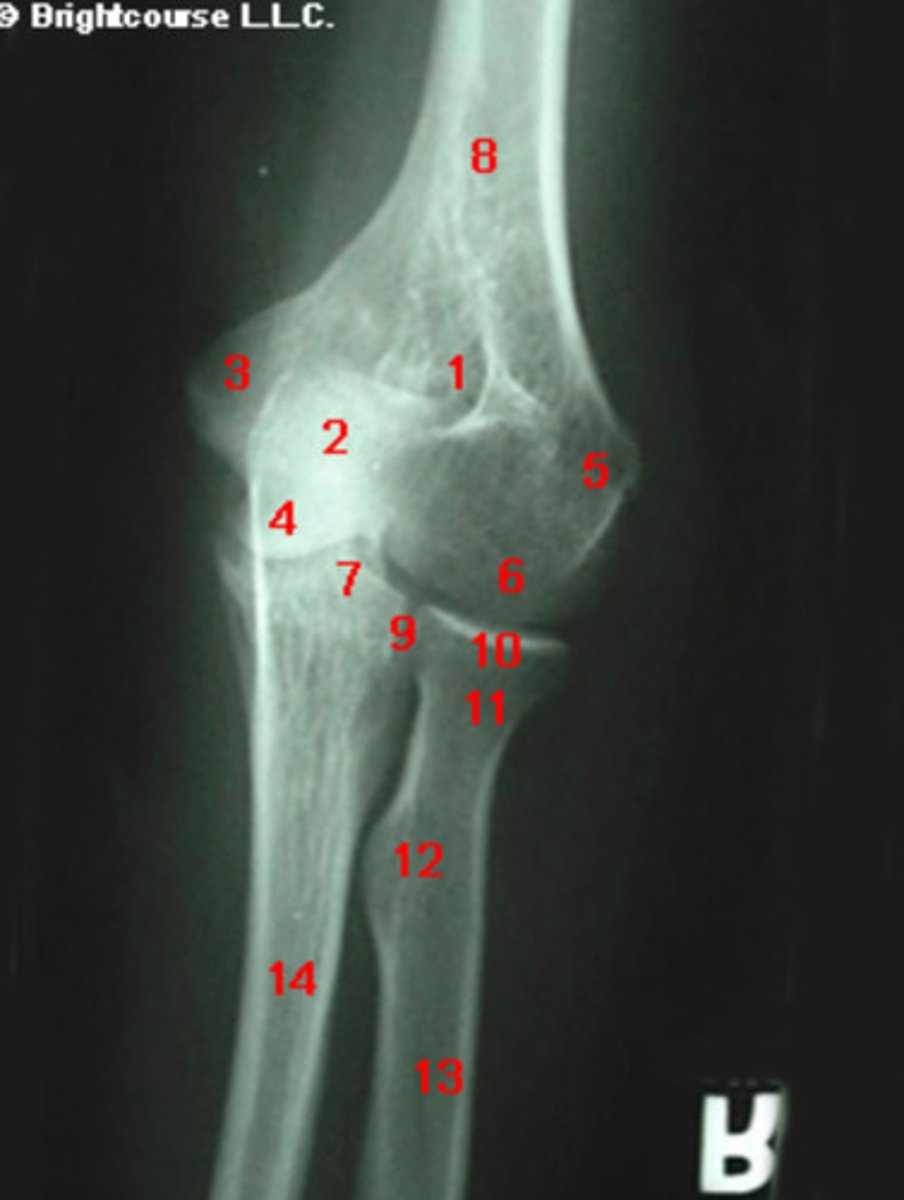

What structure is indicated by number 1?

What structure is indicated by number 3?

What structure is indicated by number 6?

What structure is indicated by number 7?

What structure is indicated by number 5?

What structure is indicated by number 11?

What structure is indicated by number 12?